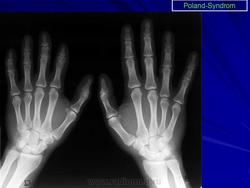

Синдром Поланда (СП) представляет собой комплекс пороков, включающий отсутствие большой и малой грудной мышц, синдактилию, брахидактилию, ателию (отсутствие соска молочной железы) и/или амастию (отсутствие самой молочной железы), деформацию или отсутствие нескольких ребер, отсутствие волос в подмышечной впадине и снижение толщины подкожно-жирового слоя. Отдельные компоненты этого синдрома впервые были описаны Lallemand LM (1826) и Frorier R (1839). Однако назван он по имени английского студента-медика Alfred Poland, который в 1841 году опубликовал частичное описание данной деформации. Полную характеристику синдрома в литературе впервые опубликовал Thompson J в 1895 году.